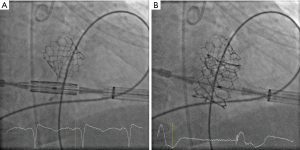

All procedures were performed under general anesthesia in the presence of our institutional Heart Team in a specially equipped hybrid operating room, offering full functionality for cardiac catheterization, anaesthesiology, and cardiac surgery, and a cardiopulmonary bypass circuit and clinical perfusion team were kept on stand-by. The transapical access was performed as previously described by our group (7) using four pledged U-stitches (Prolene 3-0, MH needle). In brief, access to the left ventricular apex was obtained by a 4–6 cm anterolateral minithoracotomy in the fourth, fifth or sixth intercostal space. After puncturing the apex, a soft guidewire was advanced under fluoroscopic guidance into the right pulmonary vein across the diseased mitral valve. Then, via a Pigtail catheter, an Extra-Stiff wire for further guidance was exchanged for the soft wire, and a transapical sheath (18–26 F sheath depending on valve type) was advanced. The reversely crimped transcatheter valve was finally deployed under ventricular overpacing (120 bpm). The landing zone was identified mainly with fluoroscopic guidance (Figures 1,2). Device function was evaluated by transesophageal echocardiography. Heparin was administered with an intended activated clotting time (ACT) time >250 s.